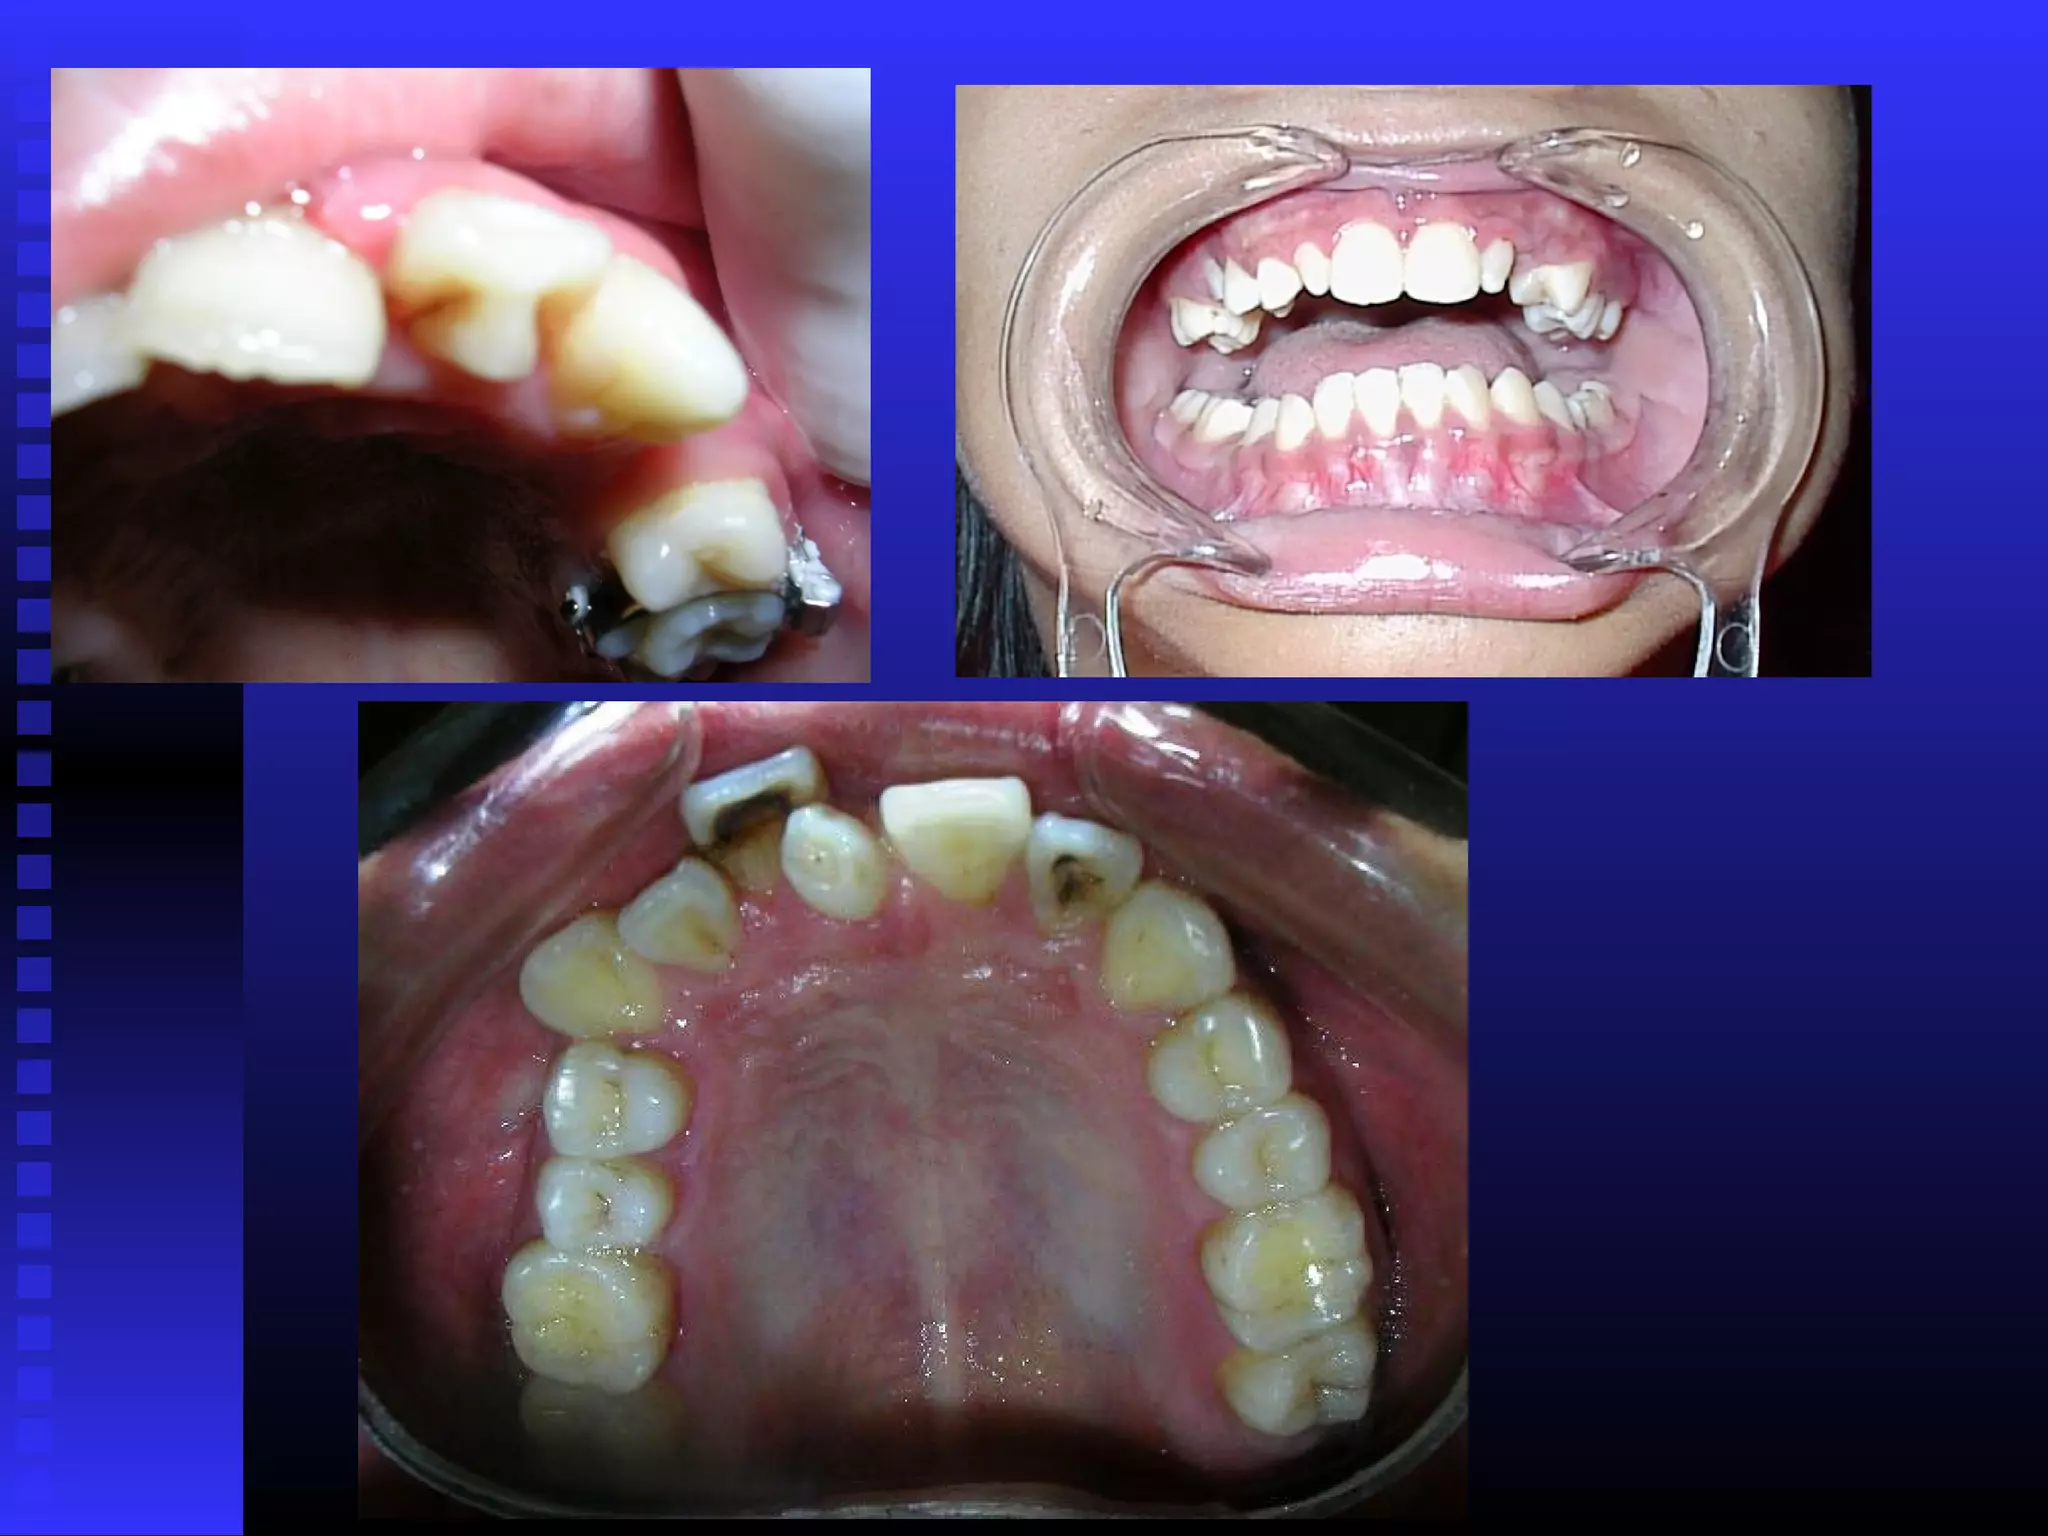

Openbite Crossbite

- Anterior openbite (the incisors are in class I relation but no

vertical overlapping)

-Usually in class I relation but may be class II or class III if

there is crowding or early loss.

• Most class I malocclusions are presenting with crowding due to

tooth size arch size discrepancy.

• Crowding may be superimposed with local factors such as early

loss ,

supernumerary.